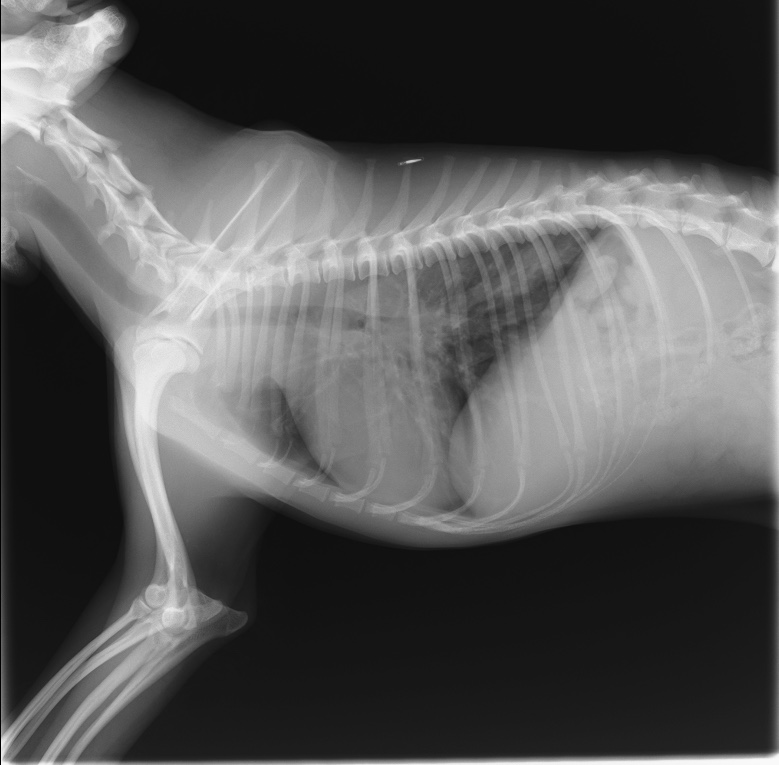

胸部レントゲン検査

胸部レントゲン検査は、呼吸器の病気について最も短時間で行うことができ、得られる情報量の多い検査です。

健康診断でご自身のレントゲン画像を見たことのある方も多いのではないでしょうか。人間のレントゲン検査と同じように、動物の体を透視したような画像を写すことができます。

レントゲンが呼吸器疾患の診断に適しているのは、レントゲンの画像が白黒の濃淡を、空気と臓器でそれぞれ異なって写すことができるためです。体の中で唯一空気を含んでいる呼吸器では、色のコントラストにより異常を判断することができます。レントゲン検査は、呼吸器のある胸の構造を観察するのに非常に有効です。

検査自体は短時間で行うことができますが、画像を撮影するのに体を抑える必要があります。犬や猫が体を抑えられることで興奮してしまうと、呼吸状態が悪い場合は命に関わることがあるため、当院では慎重に検査を行っています。